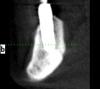

Wasja Опубликовано 10 декабря, 2012 Поделиться Опубликовано 10 декабря, 2012 Вот нарезка КТ Ссылка на комментарий

bullbull Опубликовано 27 марта, 2014 Поделиться Опубликовано 27 марта, 2014 Вот нарезка КТПри хорошем раскладе нижние простоят ещё несколько годков. А на счет верхних - сомневаюсь. Ссылка на комментарий